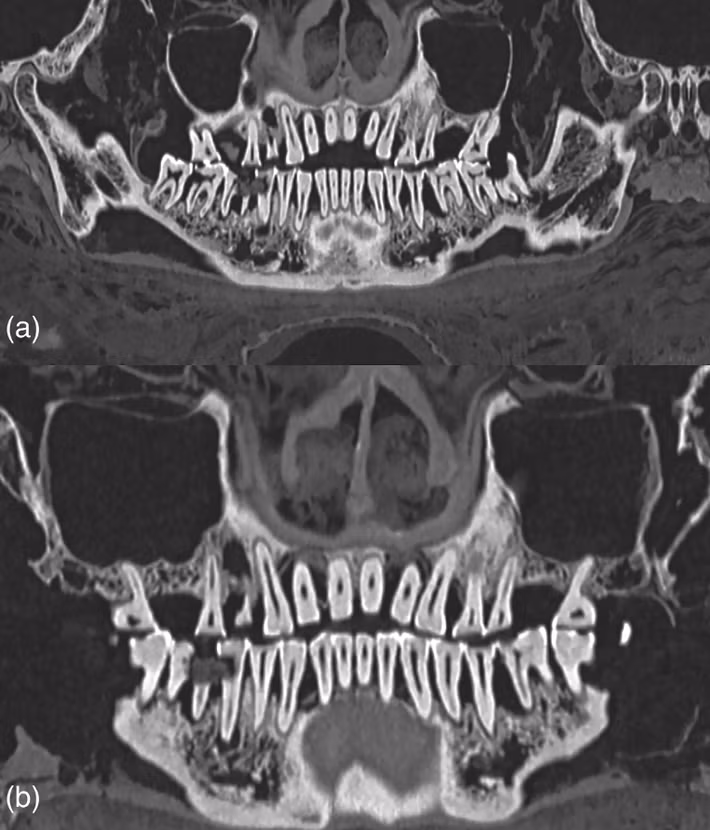

Để có được kết luận này, các chuyên gia đã sử dụng kỹ thuật chụp cắt lớp vi tính (CT) để mô tả đầy đủ về răng xác ướp Ai Cập. Ảnh: @Bảo tàng Khảo cổ học Quốc gia Athens.

Các nhà nghiên cứu đã tìm thấy một khoang xốp trong răng của xác ướp này chứa đầy vật liệu trám bảo vệ. Ảnh: @Bảo tàng Khảo cổ học Quốc gia Athens.

Ngoài ra, các nhà khảo cổ học cũng tìm thấy bằng chứng về tình trạng nhiễm trùng nướu nghiêm trọng trên xác ướp này. Nghiên cứu không tập trung vào nguyên nhân cái chết của xác ướp, nhưng đặc điểm của hộp sọ cho thấy nó thuộc về một người đàn ông trưởng thành, qua đời ở độ tuổi đôi mươi. Ảnh: @Bảo tàng Khảo cổ học Quốc gia Athens.